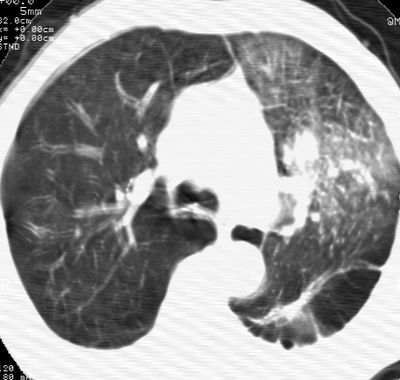

标题: CT24000:M65,胸痛,胸闷月余,既往慢支,肺气肿,肺心病 [打印本页]

标题: CT24000:M65,胸痛,胸闷月余,既往慢支,肺气肿,肺心病

左肺门肿块,相应支气管闭塞,左肺上叶、舌叶大片及散在高密度影,部分呈不张改变,两肺纹粗乱,左侧胸腔积液。考虑左侧中央型肺癌伴阻塞性改变。

左肺门见巨大软组织肿块影,直径约--,境界清,左上肺叶支气管变窄,左上肺舌叶见大片状密实影,余肺纹理增多、紊乱、纤细、部分网格状,两肺透亮度增高,纵隔内见增大多发淋巴结影,心影略左偏,左侧少量胸腔积液。

左侧中央型肺癌伴左上肺舌叶不张、纵隔淋巴结转移,左侧少量胸腔积液。